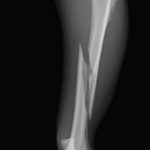

脛骨中央部らせん状骨折 階段で転んだワンチャンが、骨折をしてしまったので手術をしてほしいとの連絡があり対応しました。比較的、長い範囲でのらせん状骨折です。2本のポジションスクリューとプレーティングにより骨接合術を行いました。 症例カテゴリー 放射線治療整形外科軟部組織外科脳神経外科内科腫瘍外科救急・集中治療リハビリテーション科腫瘍内科内視鏡科脳神経科呼吸器外科中医・漢方猫の腎移植循環器科